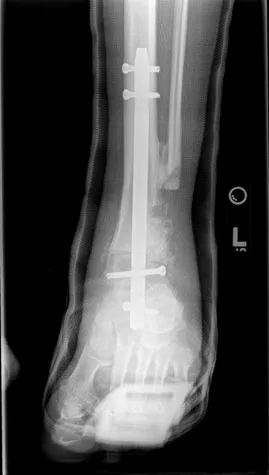

The images below are that of Charcot of the ankle joint. This patient had a wound to the inside of his ankle as he would walk and put pressure on the inside of his ankle because the foot was displaced outward. The patient had a previous ankle fracture that was repaired. However, because of the onset of Charcot neuroarthropathy, the weakening of bones did not allow the structure to hold up after the repaired ankle fracture, causing the breakdown seen in the images. One can see that excessive stress is taken on at the ankle and the screws holding the tibia and fibula together broke.

After over a year of wound care to help the wound on the inside of the ankle heal, the patient was finally stable enough to have surgery to realign the foot underneath the ankle, requiring a fusion of the ankle and subtalar joint with a surgical nail (rod).